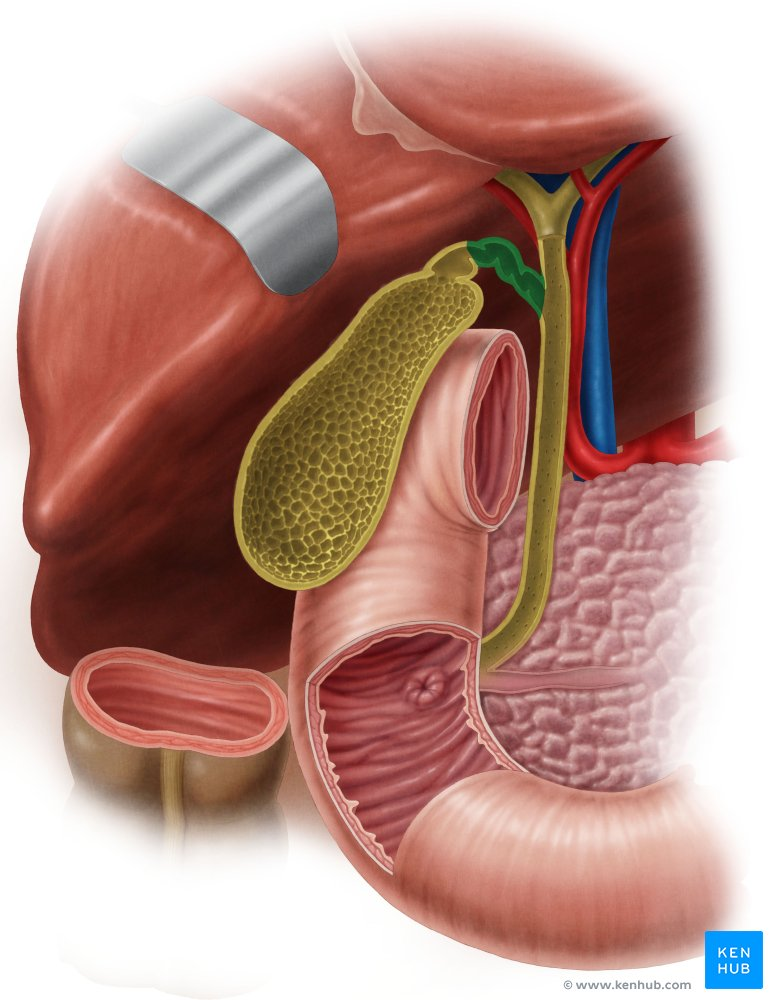

Pancreatic Duct

A duct that carries digestive enzymes produced by the pancreas to the duodenum. It typically joins with the bile duct before entering the duodenum.

Bile duct

A duct that carries bile produced by the liver and stored in the gallbladder to the duodenum, where it aids in the digestion of fats.

Gallbladder

A small, pear-shaped organ located beneath the liver that stores and concentrates bile produced by the liver.

Common Hepatic Duct

The duct formed by the union of the right and left hepatic ducts, which carries bile away from the liver.

Cystic Duct

The duct that connects the gallbladder to the common hepatic duct, allowing bile to enter and exit the gallbladder.

Hepatic Artery

A branch of the celiac artery that supplies oxygenated blood to the liver.

Hepatic Portal Vein

A large vein that carries deoxygenated but nutrient-rich blood from the digestive organs (stomach, intestines, spleen, pancreas) to the liver for processing.

Pancreatic Duct / Duct of Wirsung

The main duct that runs through the length of the pancreas, collecting digestive enzymes from the pancreatic cells and transporting them to the duodenum.

Accessory Pancreatic Duct / Duct of Santorini

A smaller pancreatic duct that branches off the main pancreatic duct and may also empty into the duodenum, usually superior to the major duodenal papilla.

Hepatopancreatic Ampulla / Ampulla of Vater

A dilated chamber formed by the joining of the common bile duct and the pancreatic duct before they enter the duodenum.

Sphincter of Hepatopancreatic Ampulla / Sphincter of Oddi

A muscular valve that surrounds the hepatopancreatic ampulla and controls the flow of bile and pancreatic juice into the duodenum.

Major Duodenal Papilla

The raised opening in the wall of the duodenum where the hepatopancreatic ampulla typically empties its contents.